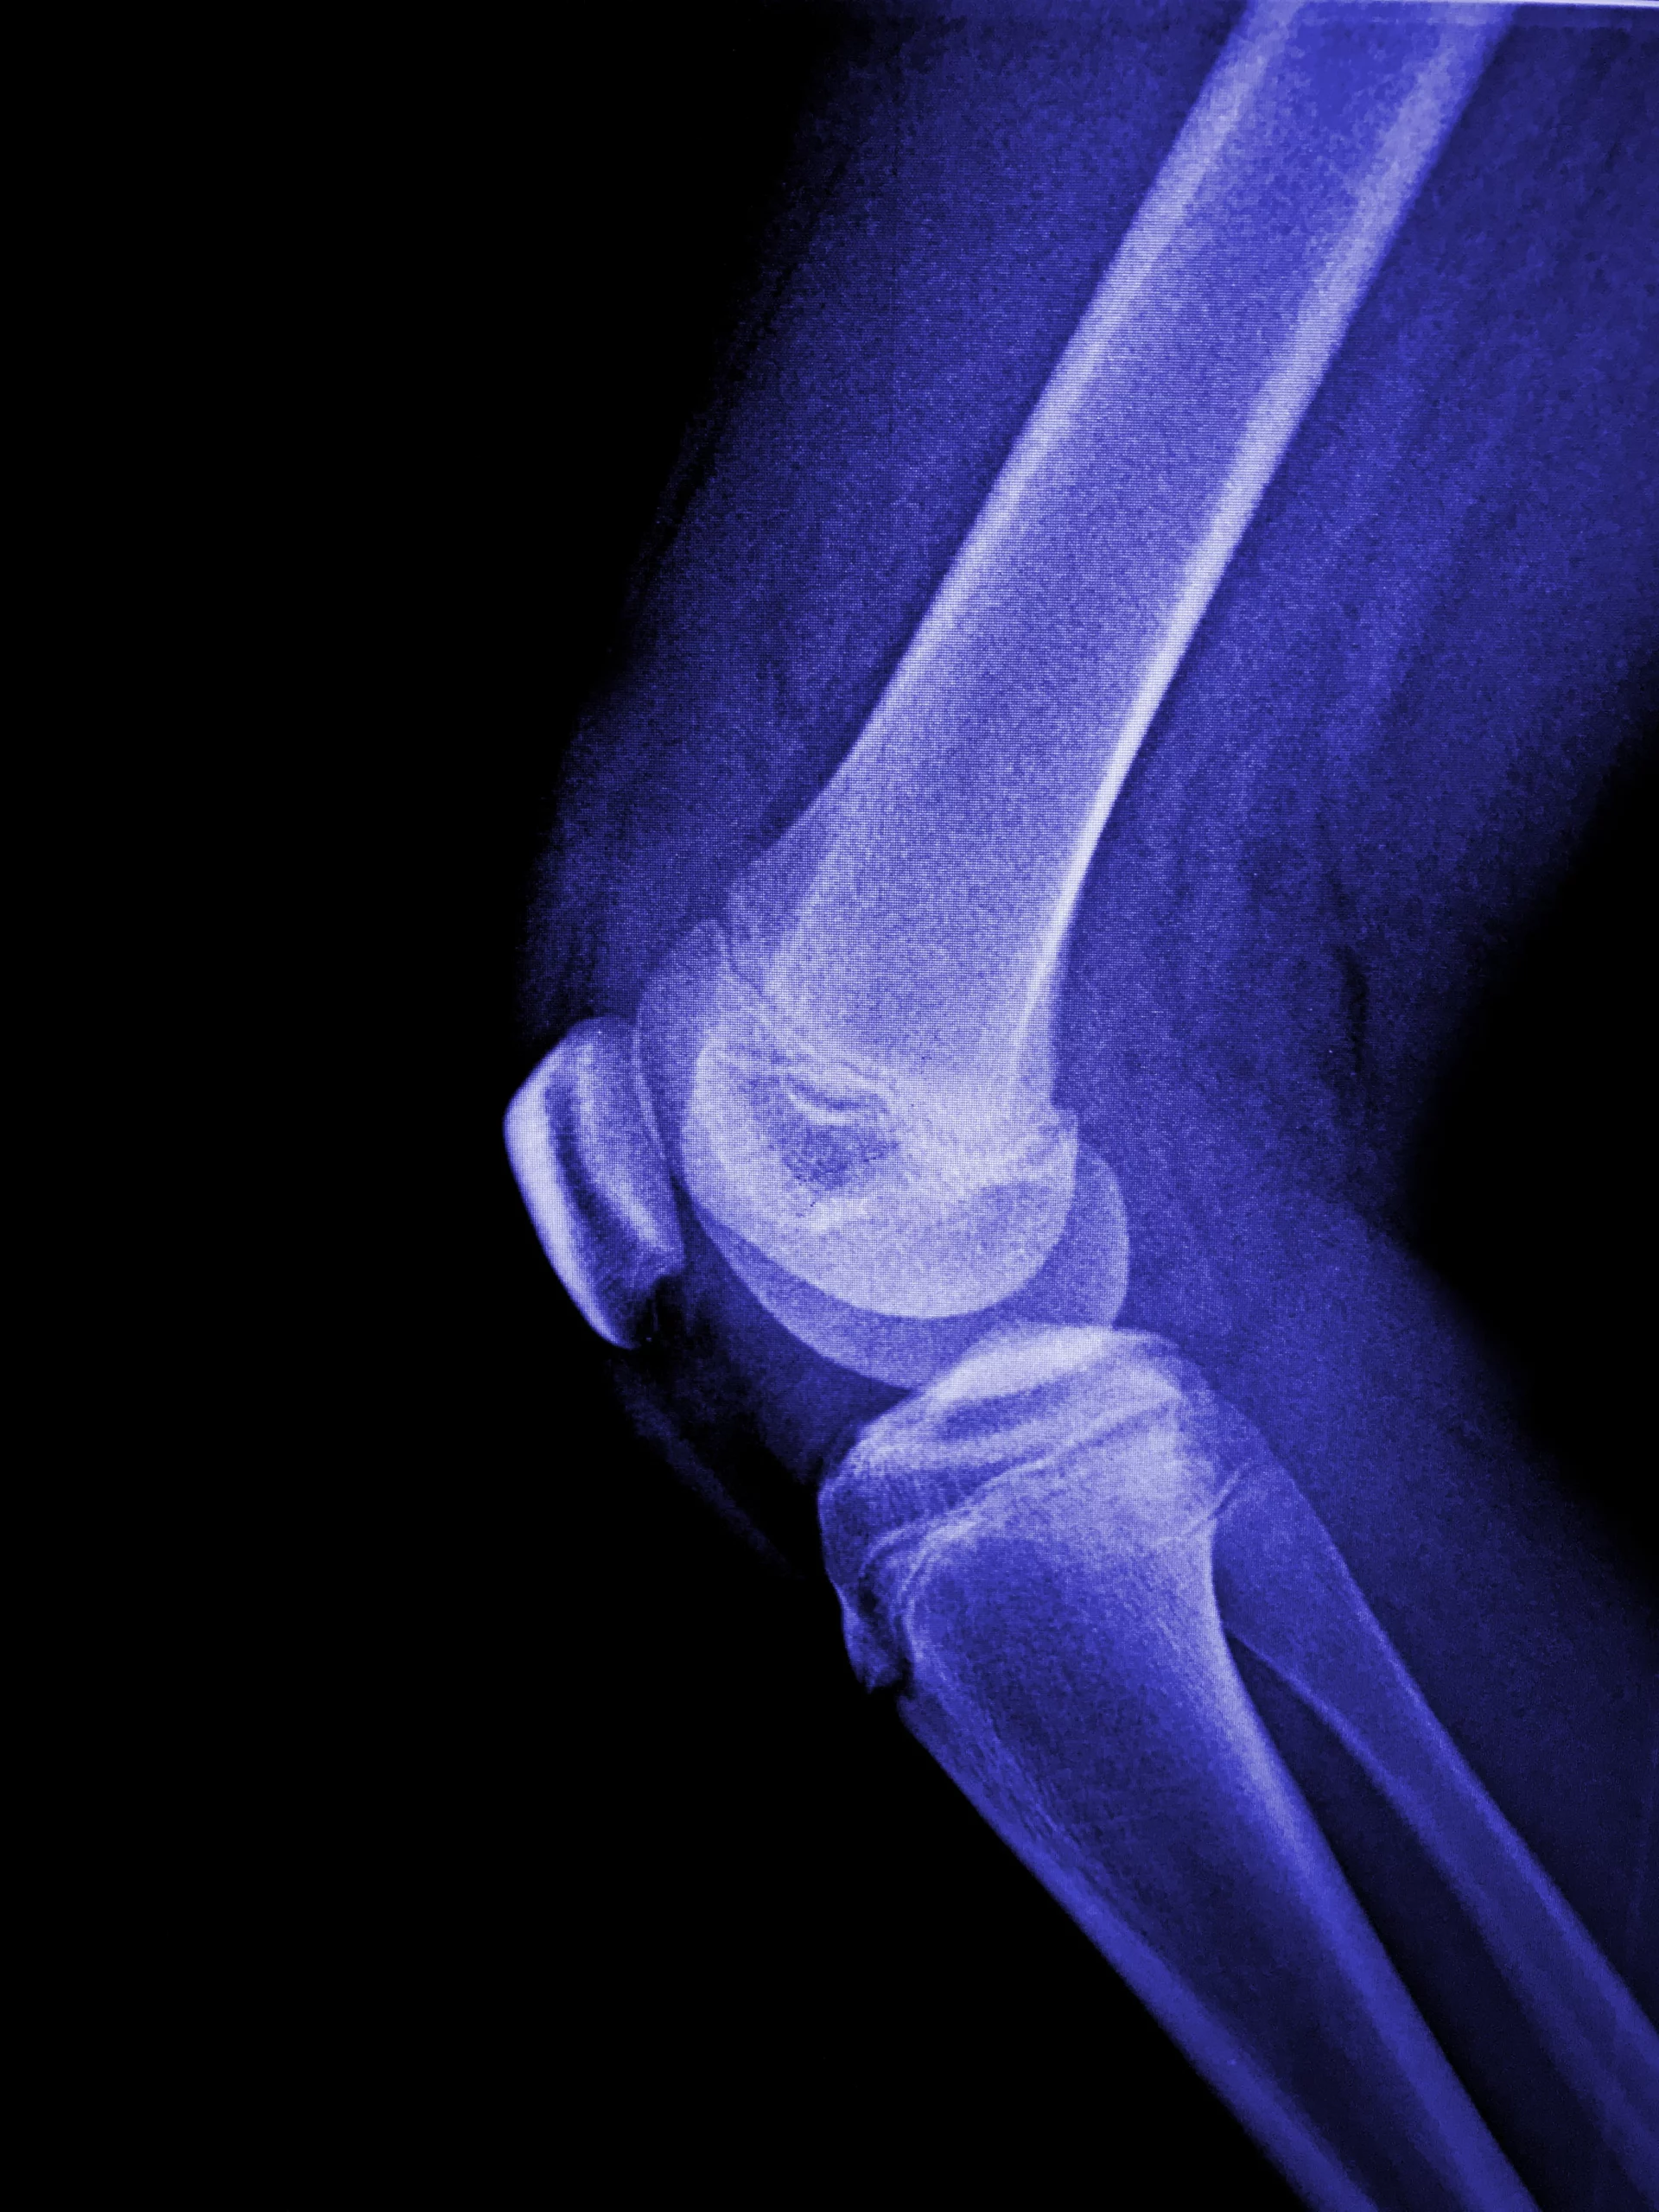

Orthrophic therapies include subchondral and intraosseous injections, primarily indicated for patients with more advanced osteoarthritis, particularly in the knee and hip. By targeting the underlying bone and joint environment, this approach aims to improve joint integrity, reduce pain, and support structural stability.

Our protocols target the subchondral bone—the vital foundation that provides oxygen and nourishment to your cartilage. By delivering umbilical cord-derived MSCs directly into this bone, we restore the biological supply lines that support joint resilience. We move beyond surface-level care to reinforce the source, arresting decay and preserving your long-term mobility.

Move better, live pain-free. Our regenerative orthopedic treatments se cutting-edge stem cell therapy to repair joints, reduce inflammation, and delay or even prevent surgery. Get back to doing what you love—without limitations.